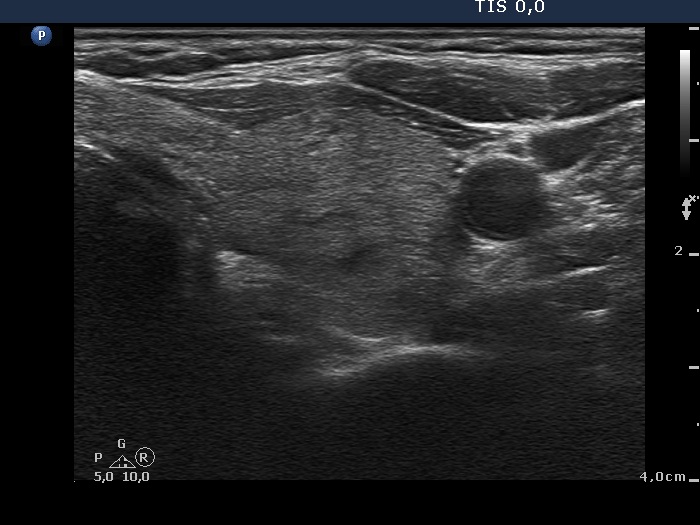

Ultrasonography. The thyroid was echonormal and had a small hypoechogenic lesion in the ventrolateral part of the right lobe. There was a hyperechogenic nodule having coarse calcification in the isthmus while the left lobe also had discrete lesions.